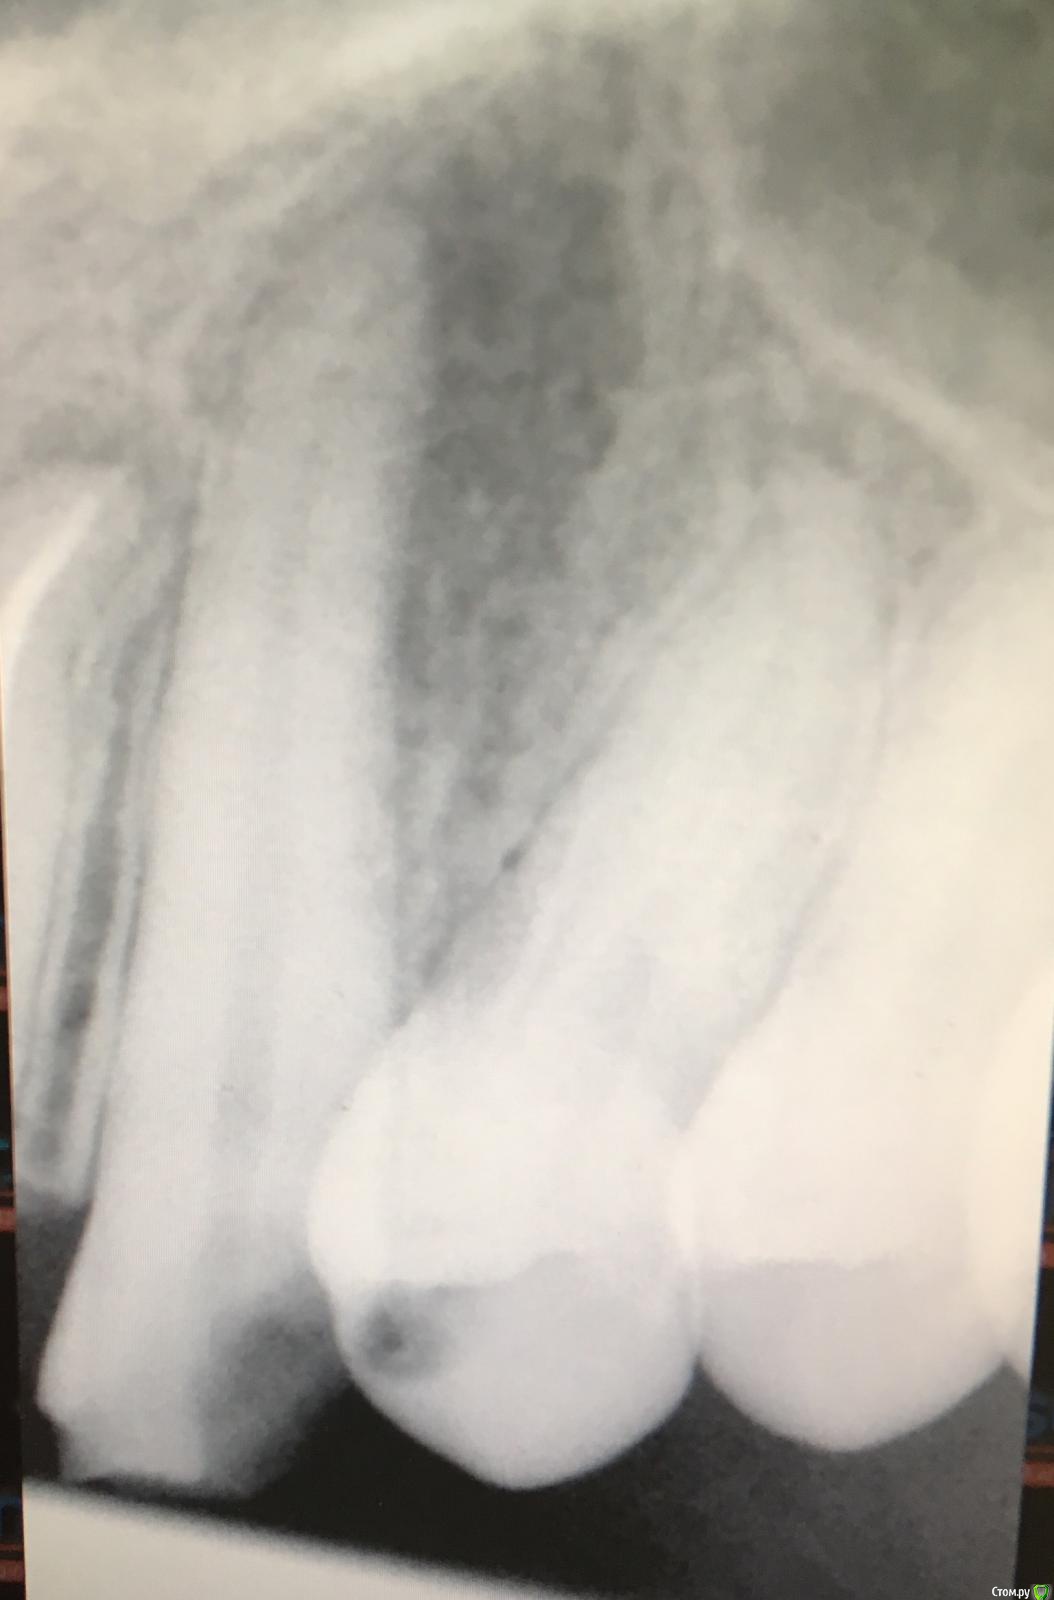

cnopmnum Опубликовано 6 октября, 2019 Поделиться Опубликовано 6 октября, 2019 Доброго времени суток. Прошу хотя бы сориентировать, в каком направлении нам двигаться дальше. Чёрные чёрточки - МЕТАЛОКЕРАМИКА, мост, то есть на 4 зубах. Чёрным выделенный зуб - под удаление, тк врач сказал, там воспаление сильное ( на всякий случай ещё рентген прикладываю этого зуба и зуба, который обведён красным кружком )Красный кружок, это зуб с метал.мост, НО под ним воспаление...Что делать? Без переднего зуба долго ходить сомнительно, снимать мост и переустанавливать его уже не на 4 зуба, а на 7 зубов, прихватив ещё с другой стороны резец( он тоже проблемный, после лечения должен остаться лишь огрызочек )? Так же все упирается в деньги, об имплантах речи сейчас даже не идёт. Или просто протез сделать на передние?? Ссылка на комментарий

dok1 Опубликовано 6 октября, 2019 Поделиться Опубликовано 6 октября, 2019 По снимку зуб подлежит лечению 2 Ссылка на комментарий

Saymon Опубликовано 6 октября, 2019 Поделиться Опубликовано 6 октября, 2019 Добрый день. Двигаться в сторону 1. Компьютерная томография2. Врач терапевт(эндодонтист), работающий с микроскопом как вариант.Зуб перелечивать, наблюдать на контрольном рентгене через 3-6 месяцев. 90% успех. Удалять и снимать мост необходимости нет. Рекомендована консультация эндодонтиста ( стоматолог терапевт) Ссылка на комментарий